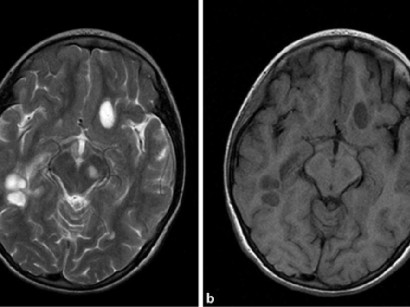

Ms Pathogenese Mrt Zeigt Inflammatorische Und Degenerative Prozesse Medical Tribune

Mrt Bei Ms Cme 1 Mrt Zur Diagnose Der Ms Um Zusatzliche Informationen Zu Erhalten Und Sie Gelangen Zur Vorherigen Folie Pdf Free Download